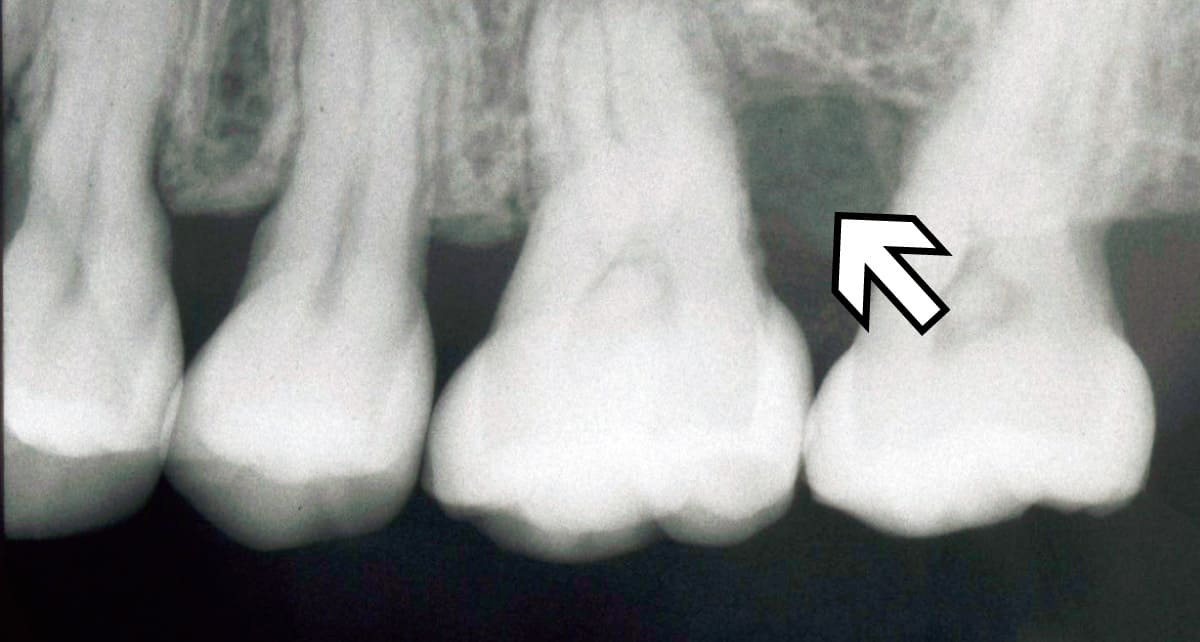

再生治療|失われた歯周組織を健康な状態に近づける。

Before

After

歯周病などでダメージを受けた歯周組織を再生させる治療。薬剤を使用して歯周組織の再生を促す方法や外科的治療を行うなど、さまざまな方法がある。歯ぐきを引き上げたり歯槽骨を再生させたりと歯の機能の改善にも役立つ。

【料金】15万円〜

【治療期間】3か月〜1年程度